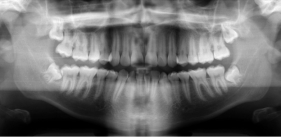

-Refer to the figure. What is the imaging method used in this image?

Panoramic radiograph